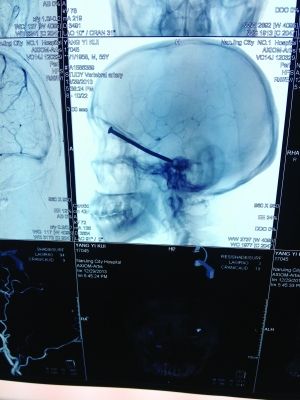

CT投影

CT投影結(jié)果,把大家嚇了一跳:楊先生腦子里居然有一根長釘,從眼眶一直“伸”到了接近后腦勺的位置!鐵釘細(xì)長略帶彎曲,長達(dá)8厘米。根據(jù)推測,鐵釘應(yīng)該是從上眼眶的縫隙中飛入,一直插進(jìn)腦顱中,末端還有一個小小凸出的釘帽。